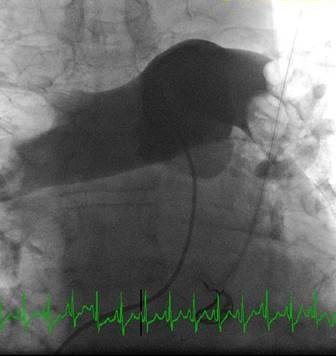

Paciente con hemorragia gastrointestinal activa que impide el uso de trombolíticos. Angiografía de la arteria pulmonar principal (más selectiva a la derecha) realizada con un catéter en espiral de 6 F en ángulo, que muestra la presencia de un trombo de gran tamaño dentro de las arterias pulmonares izquierda y derecha, y en las respectivas bifurcaciones lobares.

Se efectuó una trombectomía reolítica con el catéter PE de AngioJet® a través de una guía de angioplastia hidrófila de 0,035’’, partiendo de la arteria pulmonar izquierda y la bifurcación lobular inferior. La intervención se repitió en la arteria pulmonar derecha y en las bifurcaciones lobulares correspondientes. La intervención se detuvo debido a una bradiarritmia. Además, el tiempo de activación total se encontraba cerca del  límite recomendado (4 minutos).

A pesar del gran volumen de trombo eliminado, el angiograma final solo muestra una leve mejora de la obstrucción. Sin embargo, el objetivo del tratamiento es simplemente restaurar el flujo y no eliminar el trombo por completo, ya que incluso el modesto resultado de este angiograma estuvo acompañado de una considerable recuperación hemodinámica y de intercambio gaseoso.